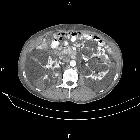

adult polycystic kidney disease (APCKD)

Autosomal dominant polycystic kidney disease (ADPKD), also sometimes more vaguely referred to as "adult polycystic kidney disease", is as the name would suggest, a hereditary form of adult cystic renal disease.

Radiographic features

Imaging of patients with autosomal dominant polycystic kidney disease can be challenging, simply due to the size and number of the cysts and associated mass effect on adjacent structures. It is potentially tedious, but necessary, to assess all cysts for atypical features, that may reflect complications (e.g. hemorrhage or infection) or malignancy (i.e. renal cell carcinoma) .

CT

CT is of course very sensitive to the diagnosis and excellent at characterizing renal cysts. Simple cysts appear as rounded structures with near water attenuation (~ 0 HU). The wall is very thin and regular, and are often imperceptible.

Cysts which have had internal complications may be hyperattenuating, with internal non-enhancing septations and/or calcifications.

A complex cystic mass with solid components or thick septa which enhance should be viewed with suspicion, and presence of a renal cell carcinoma (RCC) suspected (see Bosniak classification of renal cysts).